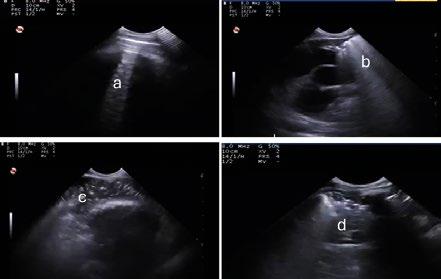

La ecografía torácica se realizó con un ecógrafo portátil (Esaote MyLab One Vet) equipado con sonda microconvexa de 10 MHz. En esta, se evaluaron secuencialmente los lóbulos pulmonares craneales, medios y caudales, categorizando las imágenes obtenidas según la aparición de:

Líneas A (patrón normal) (Imagen 2a).

Líneas B (Imagen 2b).

Consolidaciones (Imagen 2c).

Derrame pleural.

Abscesos (Imagen 2).

consolidación y (d) absceso.